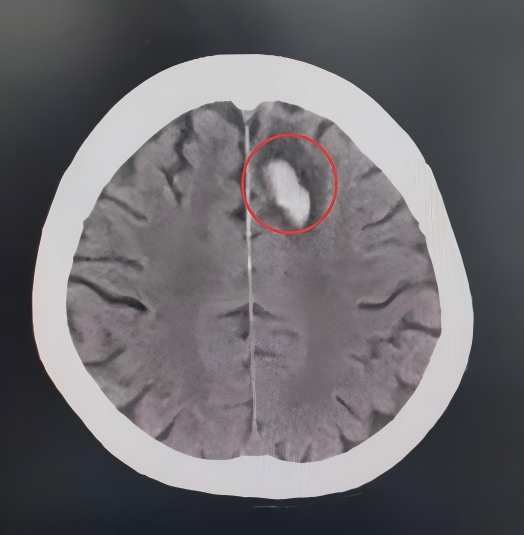

急诊团队迅速完成张大爷的心率、血压、血氧饱和度等关键指标监测。综合检查提示:老人左侧额叶脑挫裂伤,左侧股骨颈骨折,全身多处擦伤。

白色为创伤性颅内血肿,周边黑色为水肿

可以明显看到血肿和水肿范围在不断扩大

病情随时可能出现变化